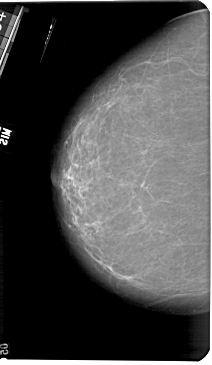

A_1182_1.LEFT_CC

LEFT_CC LINES 5461 PIXELS_PER_LINE 3166 BITS_PER_PIXEL 12 RESOLUTION 43.5 NON_OVERLAY